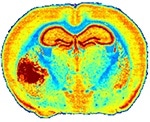

A mouse brain tissue section analysis by IR microscopy showing the anatomical details of brain with tumor (left part) based on extracellular matrix distribution. FTIR acquisition lasted 12h for a 20-µm resolution while QCL-IR acquisition could be done in 1h50 with a 4.4-µm resolution.Left: A mouse brain tissue section analysis by IR microscopy showing the anatomical details of brain with tumor (left part) based on extracellular matrix distribution. FTIR acquisition lasted 12h for a 20-µm resolution while QCL-IR acquisition could be done in 1h50 with a 4.4-µm resolution.

The image shown is down-sampled by 8x8 due to file size limitations.